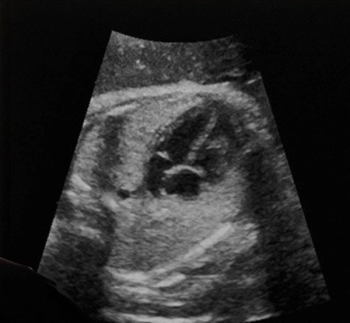

Reportedly developed on over 90,000 ultrasound exams, the BrightHeart AI software identifies suspicious findings suggestive of congenital heart defects through AI-powered evaluation of fetal heart morphology.